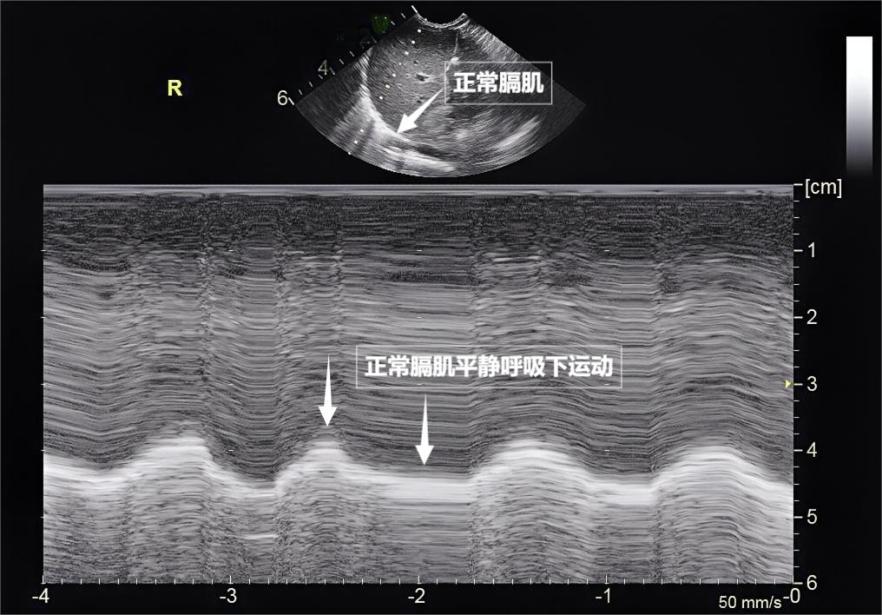

呼吸看似簡單,實則是多組肌肉精密配合的“團體操”。肺部超聲不僅能觀察肺的形態,更能通過實時動態影像,“捕捉”這些呼吸肌的活動狀態,爲評估呼吸功能提供獨特視角。膈肌是呼吸肌的“總指揮”,位於胸腔與腹腔之間。平靜呼吸時,膈肌收縮下沉,胸腔容積擴大,空氣自然吸入;舒張時,膈肌回升,肺部彈性回縮完成呼氣。超聲下可見膈肌呈光滑弧形,隨呼吸規律上下移動(見下圖)。肋間外肌則是“肋間隙的升降機”,收縮時上提肋骨,擴大胸腔前後徑,輔助吸氣。這對“黃金搭檔”承擔了日常呼吸70%以上的工作量,是維持呼吸的“主力軍”。

圖爲正常膈肌超聲表現